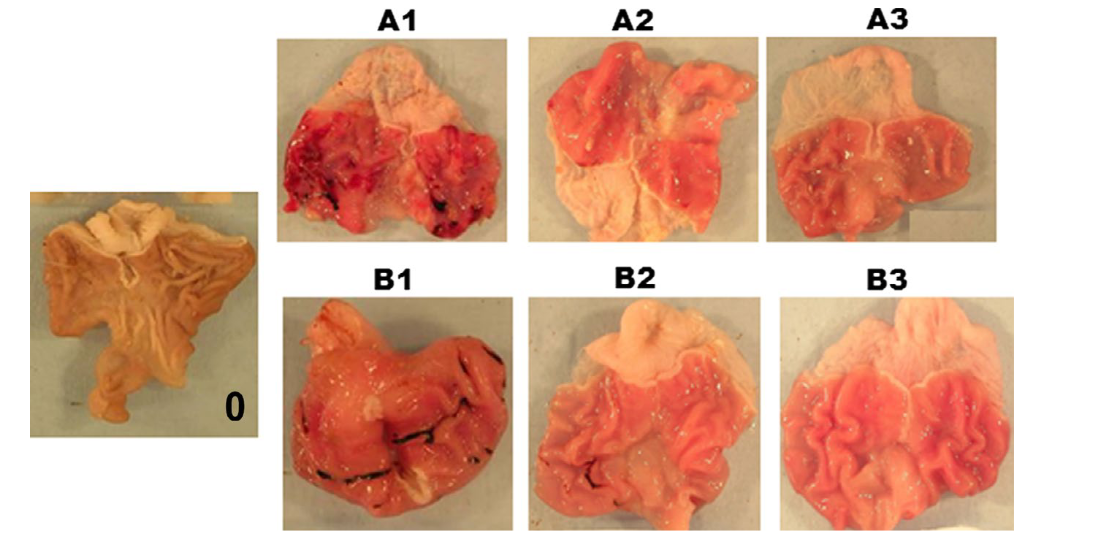

- 观察与记录:在解剖显微镜下观察胃黏膜的溃疡损伤程度。溃疡长度大于1mm者测其长度,每1mm计为1分;宽度大于1mm者则计分加倍;若为小溃疡点计0.5分。将计分相加即为该动物的溃疡指数。

损伤评估:宏观观察胃黏膜出血、糜烂灶,计算溃疡指数(UI):溃疡长度>1 mm计1分,宽度>1 mm追加1分。组织学切片(HE染色)评估黏膜上皮脱落、炎性浸润及出血深度。

- 造模后变化:一般术后3~5天即可形成胃溃疡。用此法诱发的胃溃疡,醋酸注射后第5天形成典型圆形溃疡(直径4.2±0.8 mm),深达肌层;第12天模型组愈合率仅41%,而楹树提取物组溃疡面积缩小38.4%(P<0.05),TNF-α下降43.8%。一般在60天左右可自行愈合,但也有个别在200天后仍可见较大的溃疡。溃疡的大小、深度与醋酸的浓度和注射剂量密切相关。